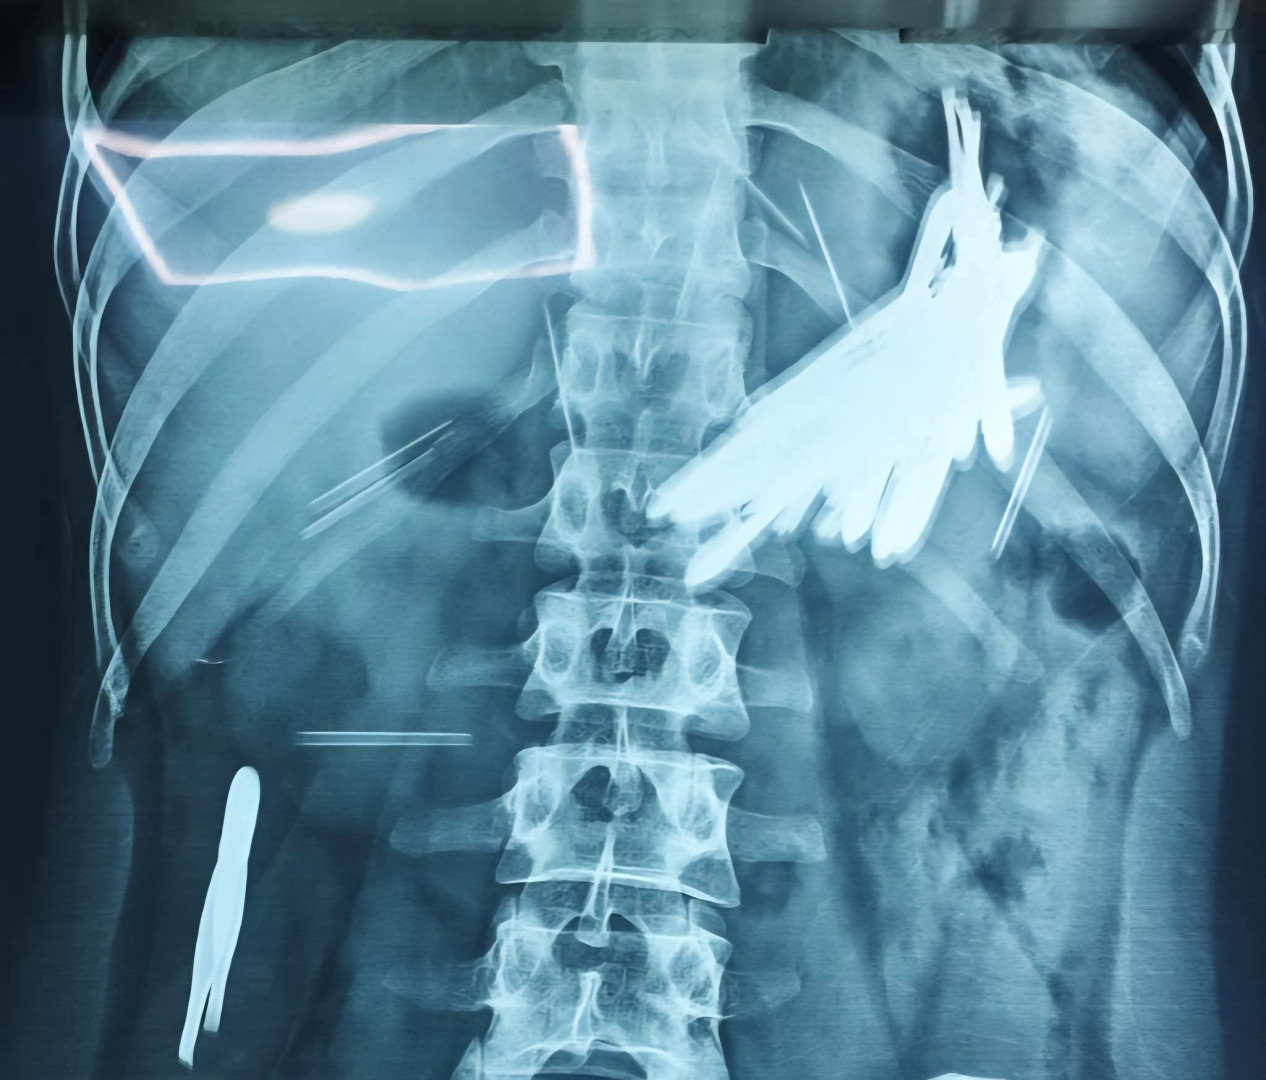

أعلن فريق طبي في مستشفى كوَراندامي التابع لمحافظة السليمانية، يوم الثلاثاء، نجاح عملية جراحية معقّدة أُجريت لشاب يبلغ من العمر 29 عاماً بعد تعرضه لإصابات بالغة.

وذكرت المديرية العامة لصحة السليمانية، في بيان ورد لوكالة شفق نيوز، أن "فريقاً طبياً متخصصاً في قسم الطوارئ والتخدير في مستشفى كوَراندامي، تمكن من إجراء عملية جراحية معقدة لإنقاذ حياة رجل يبلغ من العمر 29 عاماً".

وأضاف البيان أن "العملية شملت استخراج 16 ملقط (موكێش) و8 إبر خياطة، بالإضافة إلى قطعتين من الرصاص (بەرگی موكێش) من جسد المصاب".

وأشار إلى أن "العملية الجراحية تكللت بالنجاح، ويخضع المريض حالياً للمراقبة الصحية، وحالته مستقرة".